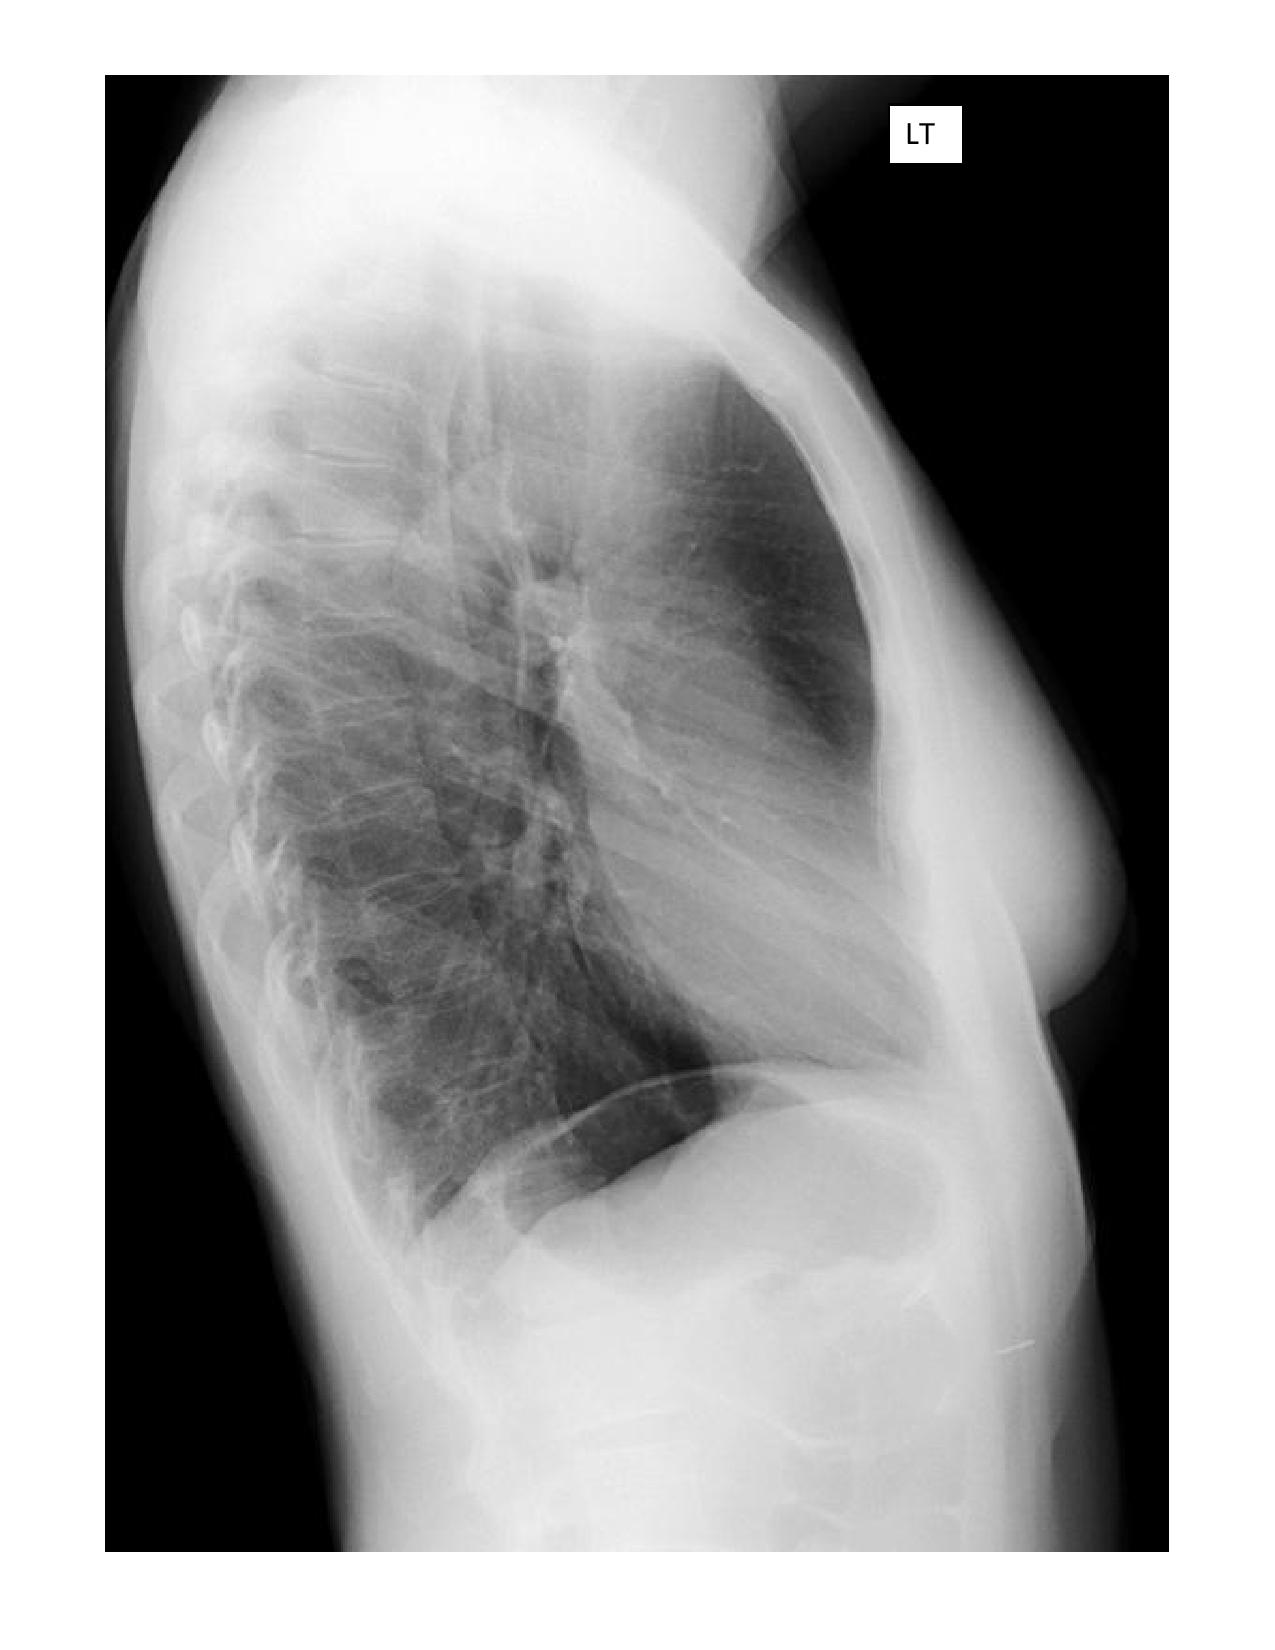

Lateral Chest

Description: Lateral chest